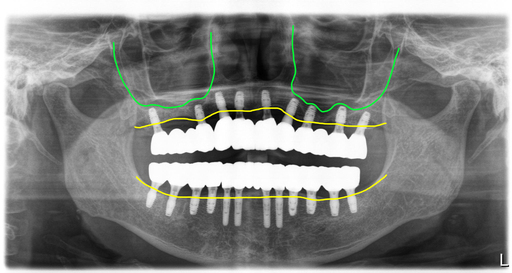

드디어 수술하는 날이 되었습니다. 보철을 제거하고 상태가 좋지 않은 치아들은 모두 제거하고 남아있는 뼈를 최대한 이용해서 뼈이식과 함께 임플란트를 식립했습니다.

위 9개, 아래 12개 식립을 했고 위에는 6개 아래는 8개에 지대주를 연결해서 수술당일 임시치아를 적용해서 즉시하중 전체임플란트 치료를 했습니다.

그래서 상악과 하악관계가 좋지 않았습니다. 수술후 이 부분을 해소하기 위해 임시치아 적용시 고경을 조절해 드렸습니다.

수술후 5개월차에 2차를 진행했습니다. 교합이 불안정해서 이 분은 스캔을 해서 맞춤지대주를 만들고 최종모양의 보철을 PMMA재료로 밀링해서 2차 당일에 끼워드렸습니다.